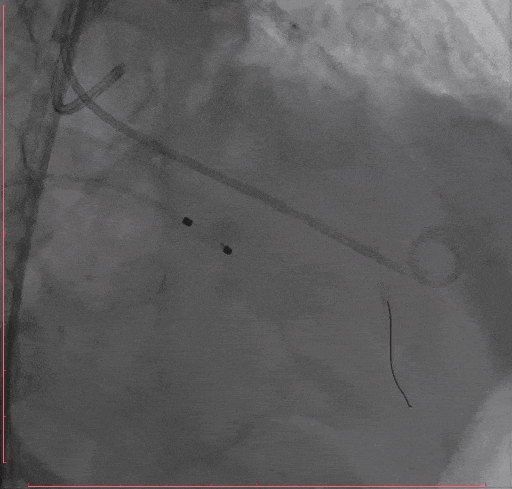

Step 3.导丝跨主动脉瓣后,干预冠脉病变,球囊无法通过LAD病变,予以旋磨

Step 4 旋磨后予以前降支支架植入